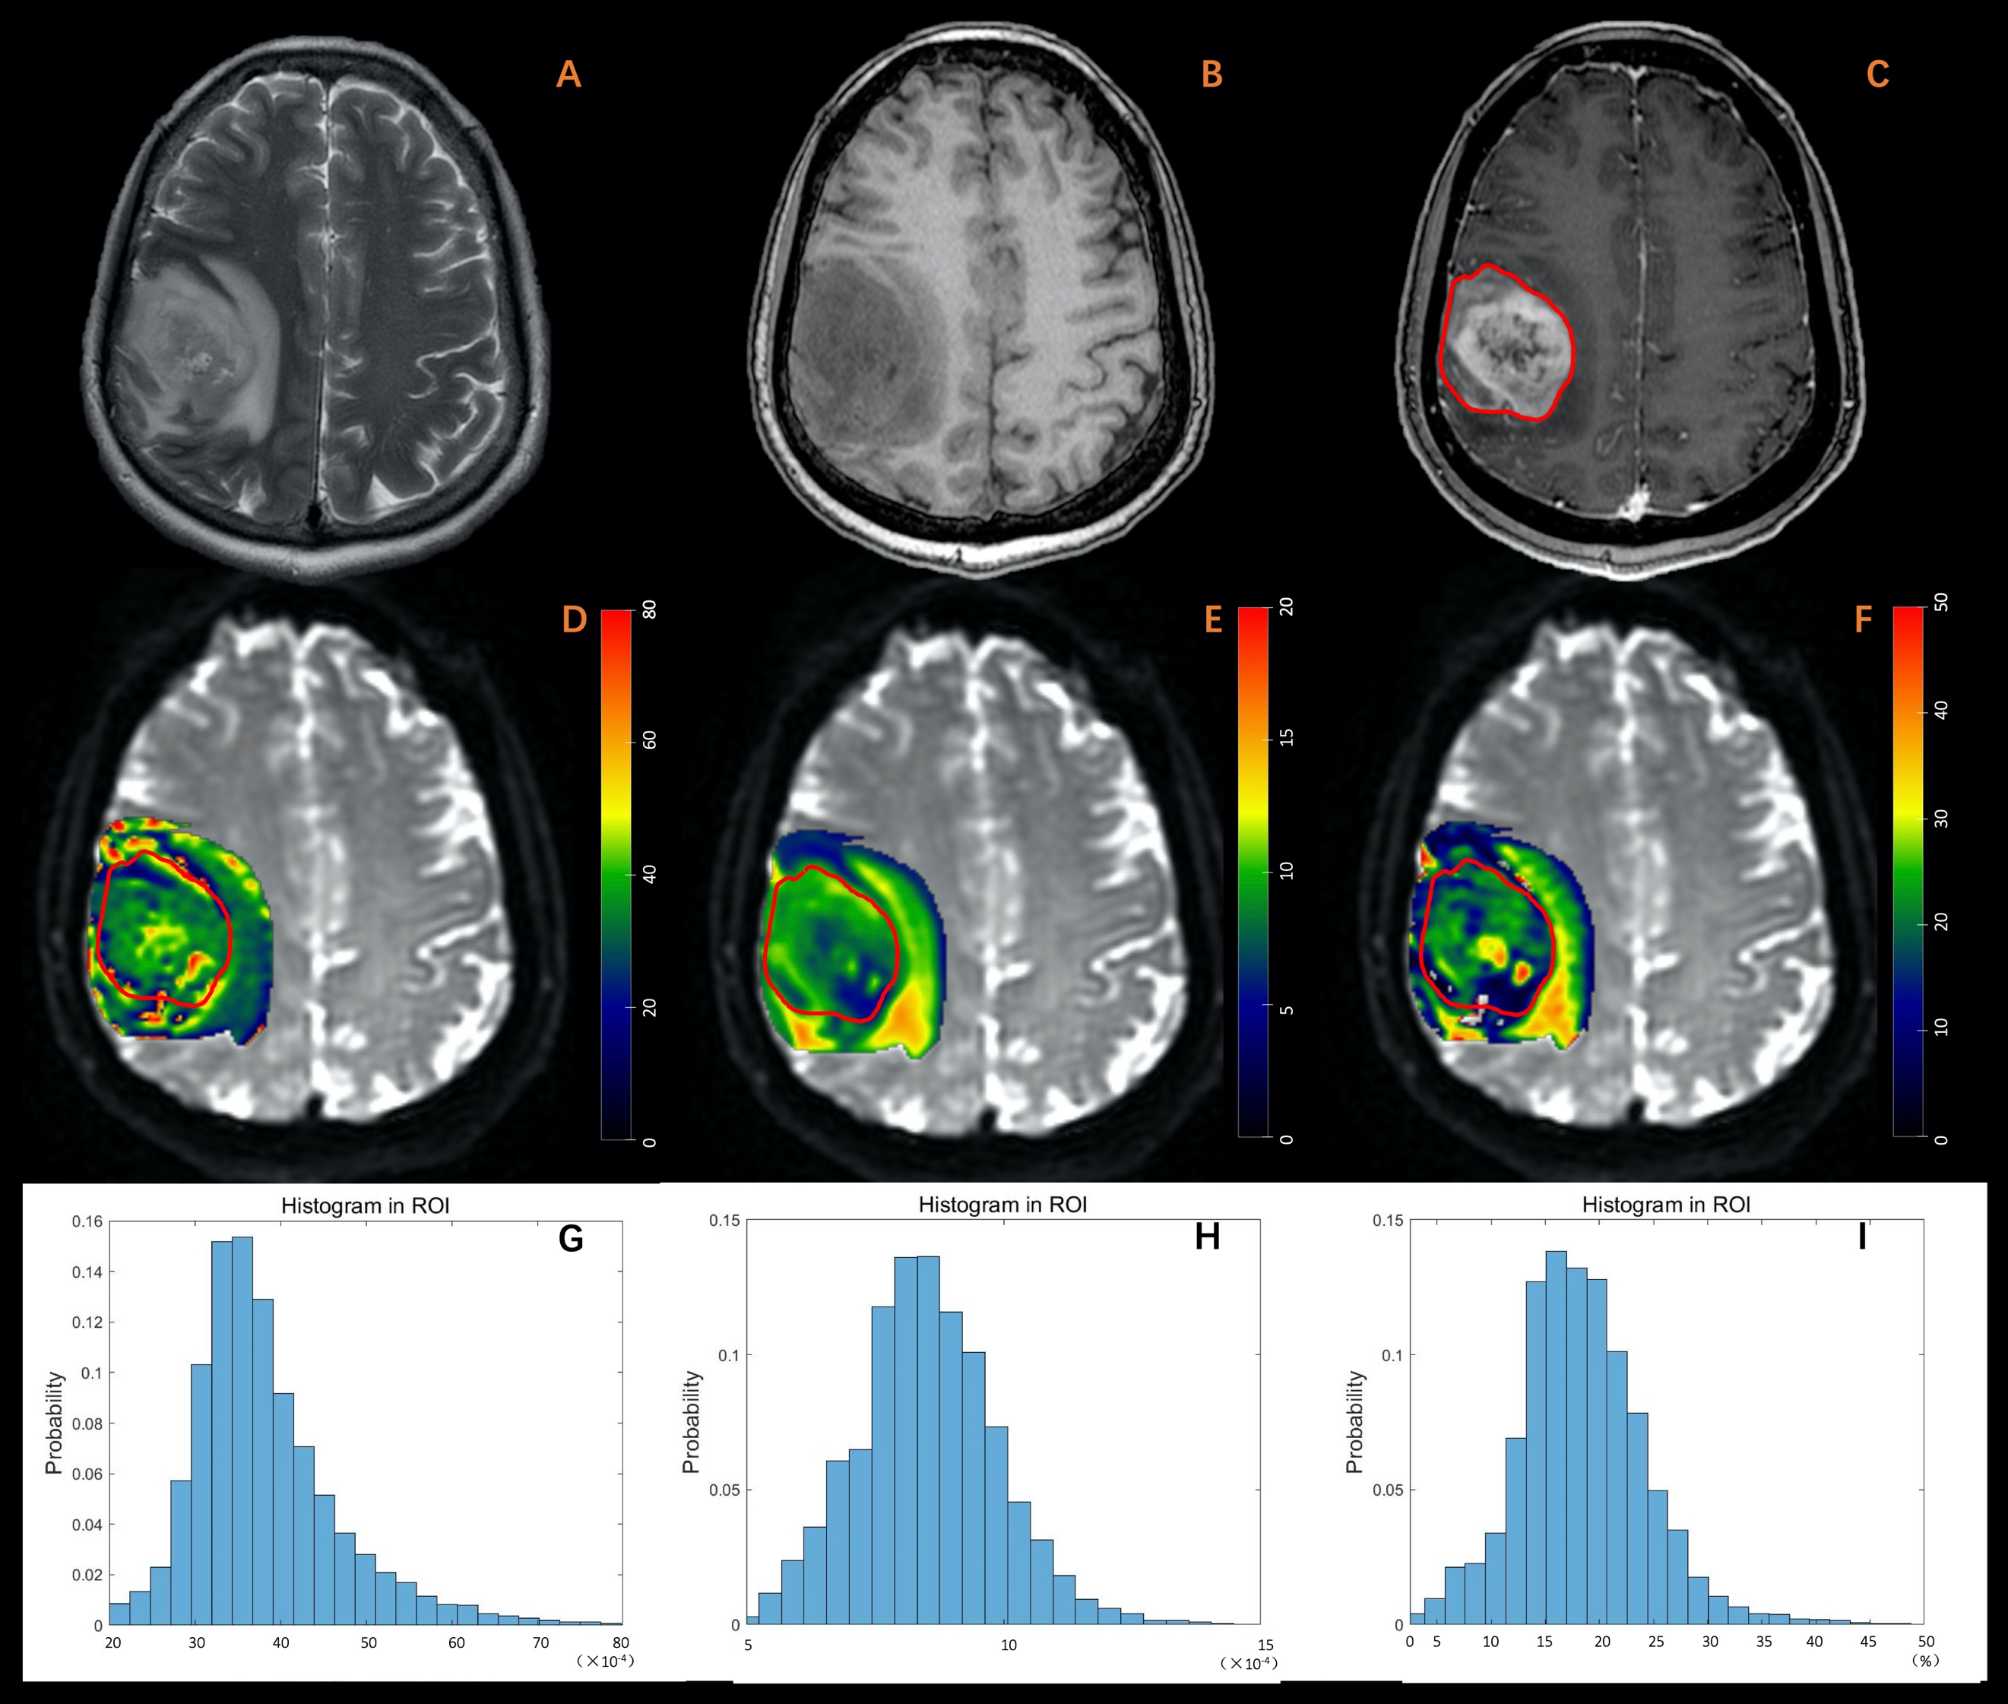

Fig. 2

A 63-year-old male diagnosed with glioblastoma. (A) T2W imaging. (B) T1W imaging. (C) Contrast-enhanced T1W imaging. (D) Dfast (×10-4mm2/s). (E) Dslow (×10-4mm2/s). (F) frac (%). (G-I) Histogram plot of Dfast, Dslow, and frac of the enhanced tumor area. The MRI examination revealed an irregular lesion in the sub-cortex of the right frontal lobe, characterized by a blurred margin. The lesion exhibited diffuse enhancement, marked in red, along with hyper-intensity on T2-weighted imaging and hypo-intensity on T1-weighted imaging. Peritumoral edema was also observed. Parametric values obtained from histogram analysis of the enhanced tumor area are as follows: Dfast: mean: 37.98, entropy: 3.19, skewness: 1.15, kurtosis: 6.60. Dslow: mean: 8.52, entropy: 3.68. skewness: 0.33, kurtosis: 3.60, frac: mean: 18.46, entropy: 3.07, skewness: 0.68, kurtosis: 5.06.